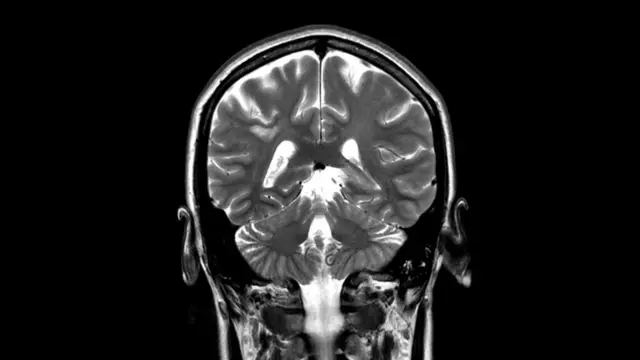

Un escáner cerebral mostró una lesión en el lado derecho de mi cerebro. No estaba claro exactamente qué significaba eso. El neurólogo me dijo que si bien podría ser una señal temprana de esclerosis múltiple, también podría ser nada de qué preocuparse.

Cuando me volví insensible a gran parte de mi cuerpo durante varias semanas, me hicieron otro escáner cerebral y finalmente me diagnosticaron EM.

Esta vez fue una nueva lesión en el tronco cerebral la causa de la recaída.

El tronco encefálico es una de las partes más importantes del cerebro: regula el sistema nervioso central y controla funciones esenciales como la respiración, la deglución, la frecuencia cardíaca, la presión arterial y la conciencia.

Una de las pruebas clave para los pacientes que participan en los ensayos o que reciben dicho tratamiento en el sistema de salud público es un escáner cerebral que debe mostrar lesiones activas e inflamatorias en el cerebro.

Mi escáner no mostró mostró lesiones activas e inflamatorias en el cerebro, sugiriendo al equipo que no sería una buena candidata para un trasplante de células madre.

Sin embargo, mi último escáner cerebral muestra que, hasta el momento, no tengo nuevas lesiones en el cerebro.